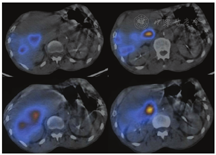

在所有患者中肝和肺之间均存在一定程度的血液分流,可能是正常分支血管、增生的肿瘤血管或动静脉畸形造成,称之为肺肝分流[26,27]。肺肝分流可在术前通过注射放射性标记的99Tcm-大颗粒聚合人血清合白蛋白(macroaggregated albumin, MAA)后计算得出一个肺内分流率的数据[28]。因99Tcm-MAA粒子的大小和分布与90Y微球相似,从而可预估对肺的潜在辐射损伤[29]。通过肝动脉导管注射多个小剂量的99Tcm-MAA(总剂量约0.148~0.185 GBq),使其分布在整个肝脏中[23,28,29]。采用腹部平面显像或SPECT(SPECT/CT)可获得术前成像(图2)[28]。计算肺内放射性示踪剂摄取的总计数,并将其除以肺和肝脏内计数的总和,从而得到肺内分流率(图3)。如果肺内分流率在单次给药剂量下大于25 Gy(树脂微球)或30 Gy(玻璃微球),或在肺中沉积的累积剂量大于50 Gy,则会对肺部造成辐射损伤风险,此时90Y微球选择性内放射治疗就属于禁忌证(图4)[30]。

注射90Y 24 h内,需进行SPECT/CT显像,以确保90Y微球已经沉积在适当的肝脏区域[31]。应观察放射性区域与术前99Tcm-MAA SPECT/CT显像一致,而肝脏外区域无放射性(图2)。SPECT/CT和平面显像通常是通过双探头的γ照相机获得[30]。